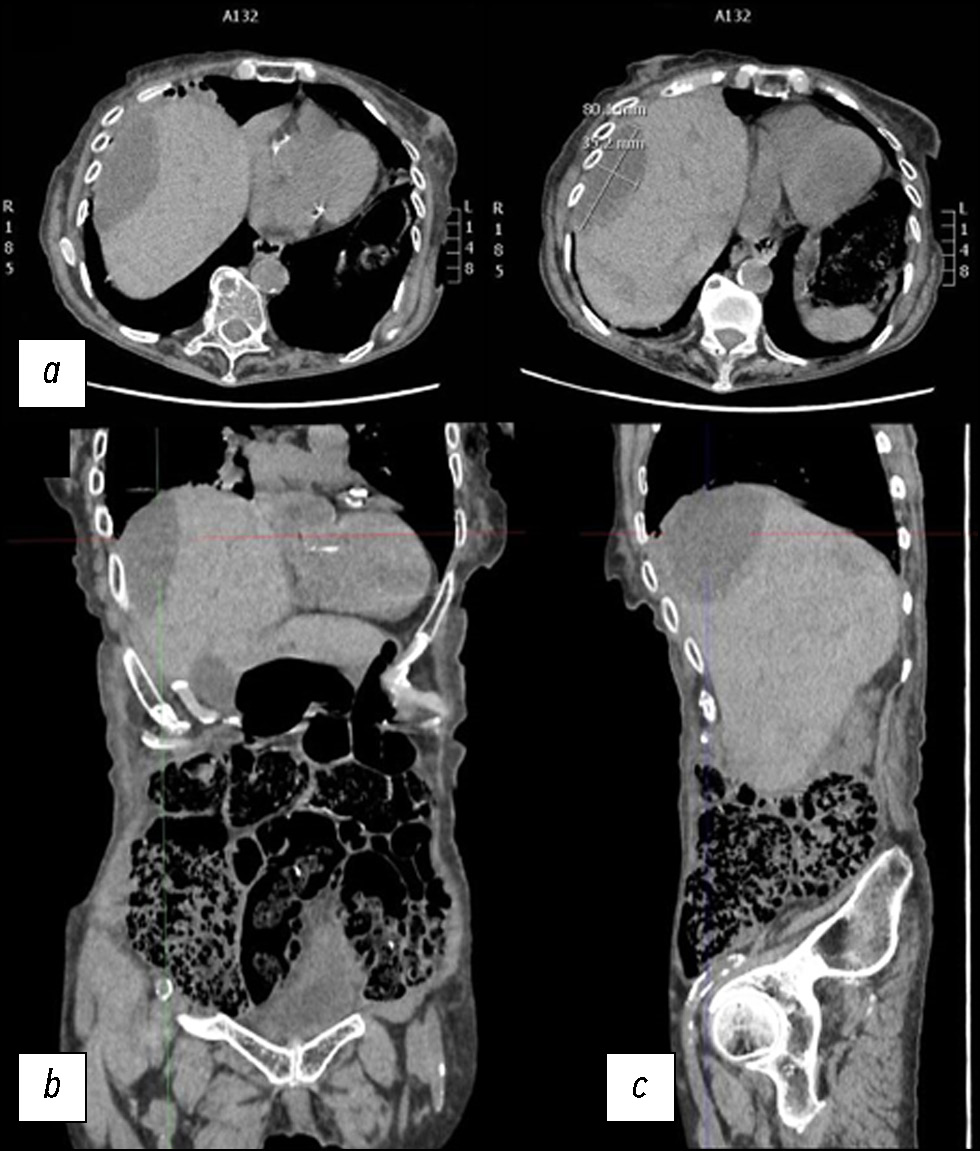

肝实质破裂是一种罕见但可能致命的疾病,可由外伤、医源性因素、自发性原因等引起。 本文通过一个病例报告,介绍了在治疗一名自发性肝实质破裂患者时所采用的诊断和治疗措施。一名老年妇女因弥漫性腹痛被送入急诊科。临床检查后,她接受了计算机断层扫描。第一次计算机断层扫描的结果并未发现全面的实质破裂。由于腹痛可能由肾绞痛或胆绞痛引起,已知信息模糊,因此早期诊断非常困难。在肝实质中只发现了几个椭圆形低密度肿块,肿块内充满了密度增高的液体。然而,疼痛持续了数天,由于患者病情恶化,进行了补充的放射检查,结果显示肝实质破裂。因此有必要进一步进行动脉造影,并延长住院时间,直到临床症状缓解。